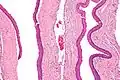

Intermediate magnification of an odontogenic keratocyst showing a folded cyst. -

Odontogenic keratocysts have a diagnostic histological appearance. Under the microscope, OKCs vaguely resemble keratinized squamous epithelium;[15] however, they lack rete ridges and often have an artifactual separation from their basement membrane.[2]

The fibrous wall of the cyst is usually thin and uninflamed. The epithelial lining is thin with even thickness and parakeratinised with columnar cells in the basal layer which have focal reverse polarisation (nuclei are on the opposite pole of the cell).[13] The basal cells are an indication of the odontogenic origin as they resemble pre-ameloblasts. The epithelium can separate from the wall, resulting in islands of epithelium. These can go on to form 'satellite' or 'daughter' cysts, leading to an overall multilocular cyst.[10] Presence of daughter cysts is particularly seen in those with NBCCS.[13] Inflamed cysts show hyperplastic epithelium which is no longer characteristic of OKCs and can have resemblance to radicular cysts instead. Due to areas of focal inflammation, a larger biopsy is required for correct diagnosis of odontogenic keratocysts.[10]